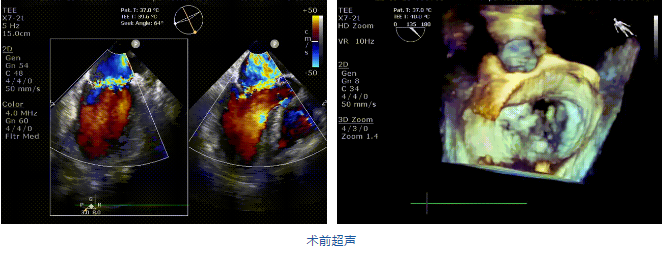

接受治療的是一例二尖瓣重度反流的患者,主訴“突發(fā)間歇性胸悶,氣急6天”。術(shù)前超聲提示:1.二尖瓣脫垂伴重度關(guān)閉不全(瞬時(shí)量30ml);2.左心、右房增大(左房容積110ml,左室容積129ml,右房容積55ml);3.左室收縮功能正常?;颊咴诔浞謽?biāo)準(zhǔn)化藥物治療后(GDMT)仍然癥狀明顯,韓林教授及其團(tuán)隊(duì)唐楊烽教授,以及心超科的周廣為醫(yī)生決定使用我國創(chuàng)新器械JensClip為患者進(jìn)行二尖瓣緣對(duì)緣修復(fù)手術(shù)。

在阜外醫(yī)院潘湘斌教授團(tuán)隊(duì)的支持下,手術(shù)經(jīng)股靜脈-房間隔入路,采用全身麻醉插管,在TEE和DSA引導(dǎo)下完成房間隔穿刺。置入JensClip瓣膜夾系統(tǒng)后,在左房調(diào)整瓣膜夾的位置和軸向,后進(jìn)入左室,在TEE引導(dǎo)下捕捉二尖瓣前后瓣葉,并關(guān)閉瓣膜夾。經(jīng)TEE反復(fù)確認(rèn)手術(shù)效果后最終鎖定并釋放瓣膜夾。術(shù)后即刻超聲顯示瓣膜夾位置穩(wěn)定,功能良好,二尖瓣反流由術(shù)前4+減少至微量,手術(shù)圓滿成功。